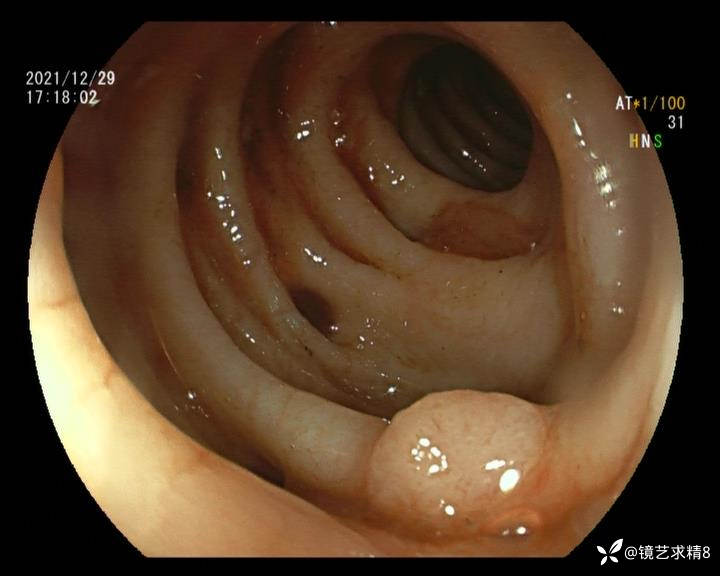

患者以消化道出血入院,胃镜未见异常,肠镜进入乙状结肠就看到很多憩室,同时还看到肠腔用清肠药后移动下来1枚尖锐的枣核,这么多憩室,这个枣核扎入憩室的机会非常大,推测应该是掉入一坑🕳就算出来还会有很多坑🕳🕳🕳等着,掉入憩室内很容易刺破血管,这可能就是消化道出血的原因,继续前进可以看到有一些憩室内翻,还有一些息肉,问题来了,那么多憩室,犯罪分子是抓住了,它在那些憩室内作过案?到达回盲部后挨个冲洗,但憩室大小又不足以把镜头进入憩室内观察,针对有血块的憩室冲洗后可疑出血的以夹子闭合或套扎,取出枣核,如果有锥形透明帽可能钻入憩室精准电凝效果更好,若内镜下操作失败介入治疗成功率更高,经内镜下治疗后观察未再出血出院。